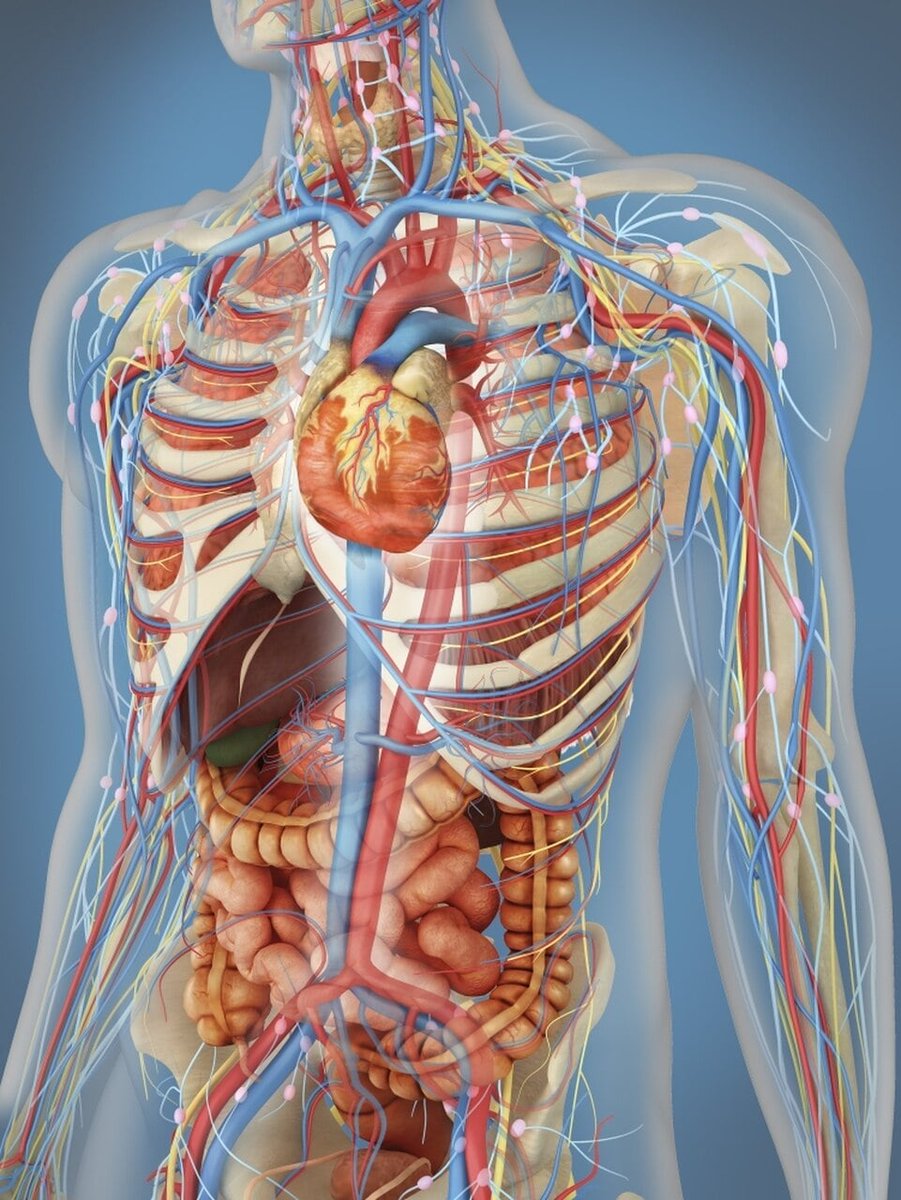

_ Datos que no debes olvidar. 1: Número de huesos: 206 2: Número de músculos: 639-650 3: Número de riñones: 2 4: Número de dientes de leche: 20 5: Número de costillas: 24 (12 pares) 6: Número de cámaras del corazón: 4 7: Arteria más grande: Aorta 8: Presión arterial…